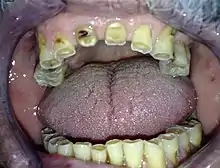

Teeth which have been severely worn down due to bruxism

1. (dentistry) The habit or practice of grinding the teeth, as while sleeping, or due to stress or certain drugs.